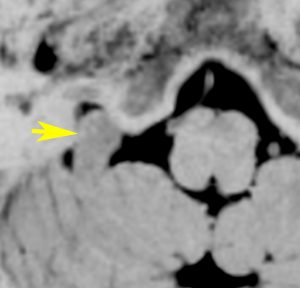

脊髄根 spinal rootから発生した無症候性の副神経鞘腫です。神経根は脊髄前根からでて脊髄の外側から背側へと上行するので,脊髄を横から圧迫するようになります。

徐々に増大しました。手術摘出を行うときに副神経を温存できないと,胸鎖乳突筋と僧帽筋の麻痺が生じます。